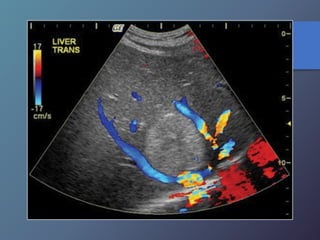

Anomalías Vasculares

• Presión normal de la porta: 5-10mmhg (14cm de agua).

• Se define como presión directa de la vena porta superior a

10mmhg.

• Puede dividirse en pre sinusoidal cuya causa mas frecuente

es la trombosis de la vena porta o esplénica.

• La cirrosis es la causa mas frecuente de hipertensión portal

intrahepatica.

• Características ecográficas: signos secundarios de

esplenomegalia, ascitis, colaterales venosas porto sistémicas.

• Se produce un aumento igual o mayor a 1.3cm.

Hipertensión Portal:

Anomalías Vasculares • Presiónnormal de la porta: 5-10mmhg (14cm de agua). • Se define como presión directa de la vena porta superior a 10mmhg. • Puede dividirse en pre sinusoidal cuya causa mas frecuente es la trombosis de la vena porta o esplénica. • La cirrosis es la causa mas frecuente de hipertensión portal intrahepatica. • Características ecográficas: signos secundarios de esplenomegalia, ascitis, colaterales venosas porto sistémicas. • Se produce un aumento igual o mayor a 1.3cm. Hipertensión Portal: